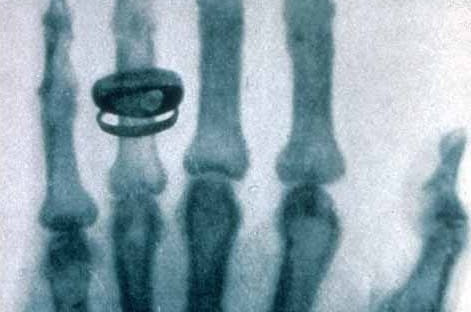

Radiation Biology (1/5): On the Trail of Ionising Radiation

The discovery of X-rays triggered an explosion of interest. The euphoria was, however, tempered as more and more information became known about the side effects. Radiation biology examines how radiation acts on cells and tissues.